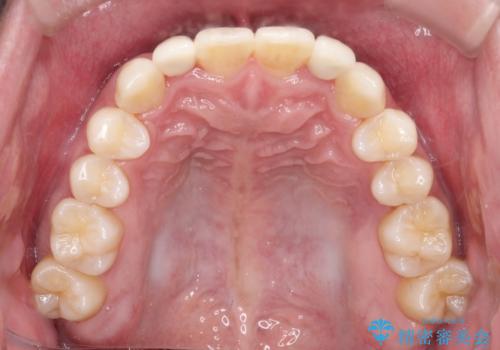

- 前歯のがたつきが気になるとのことで来院されました。

骨格的なところと、上下の歯の大きさのことを考慮して、下の前歯を1本抜歯し、インビザラインにて矯正治療することとなりました。

上の前から2番目の歯がもともと小さかったため、最後にかぶせ物を装着することで、自然な仕上がりにできました。